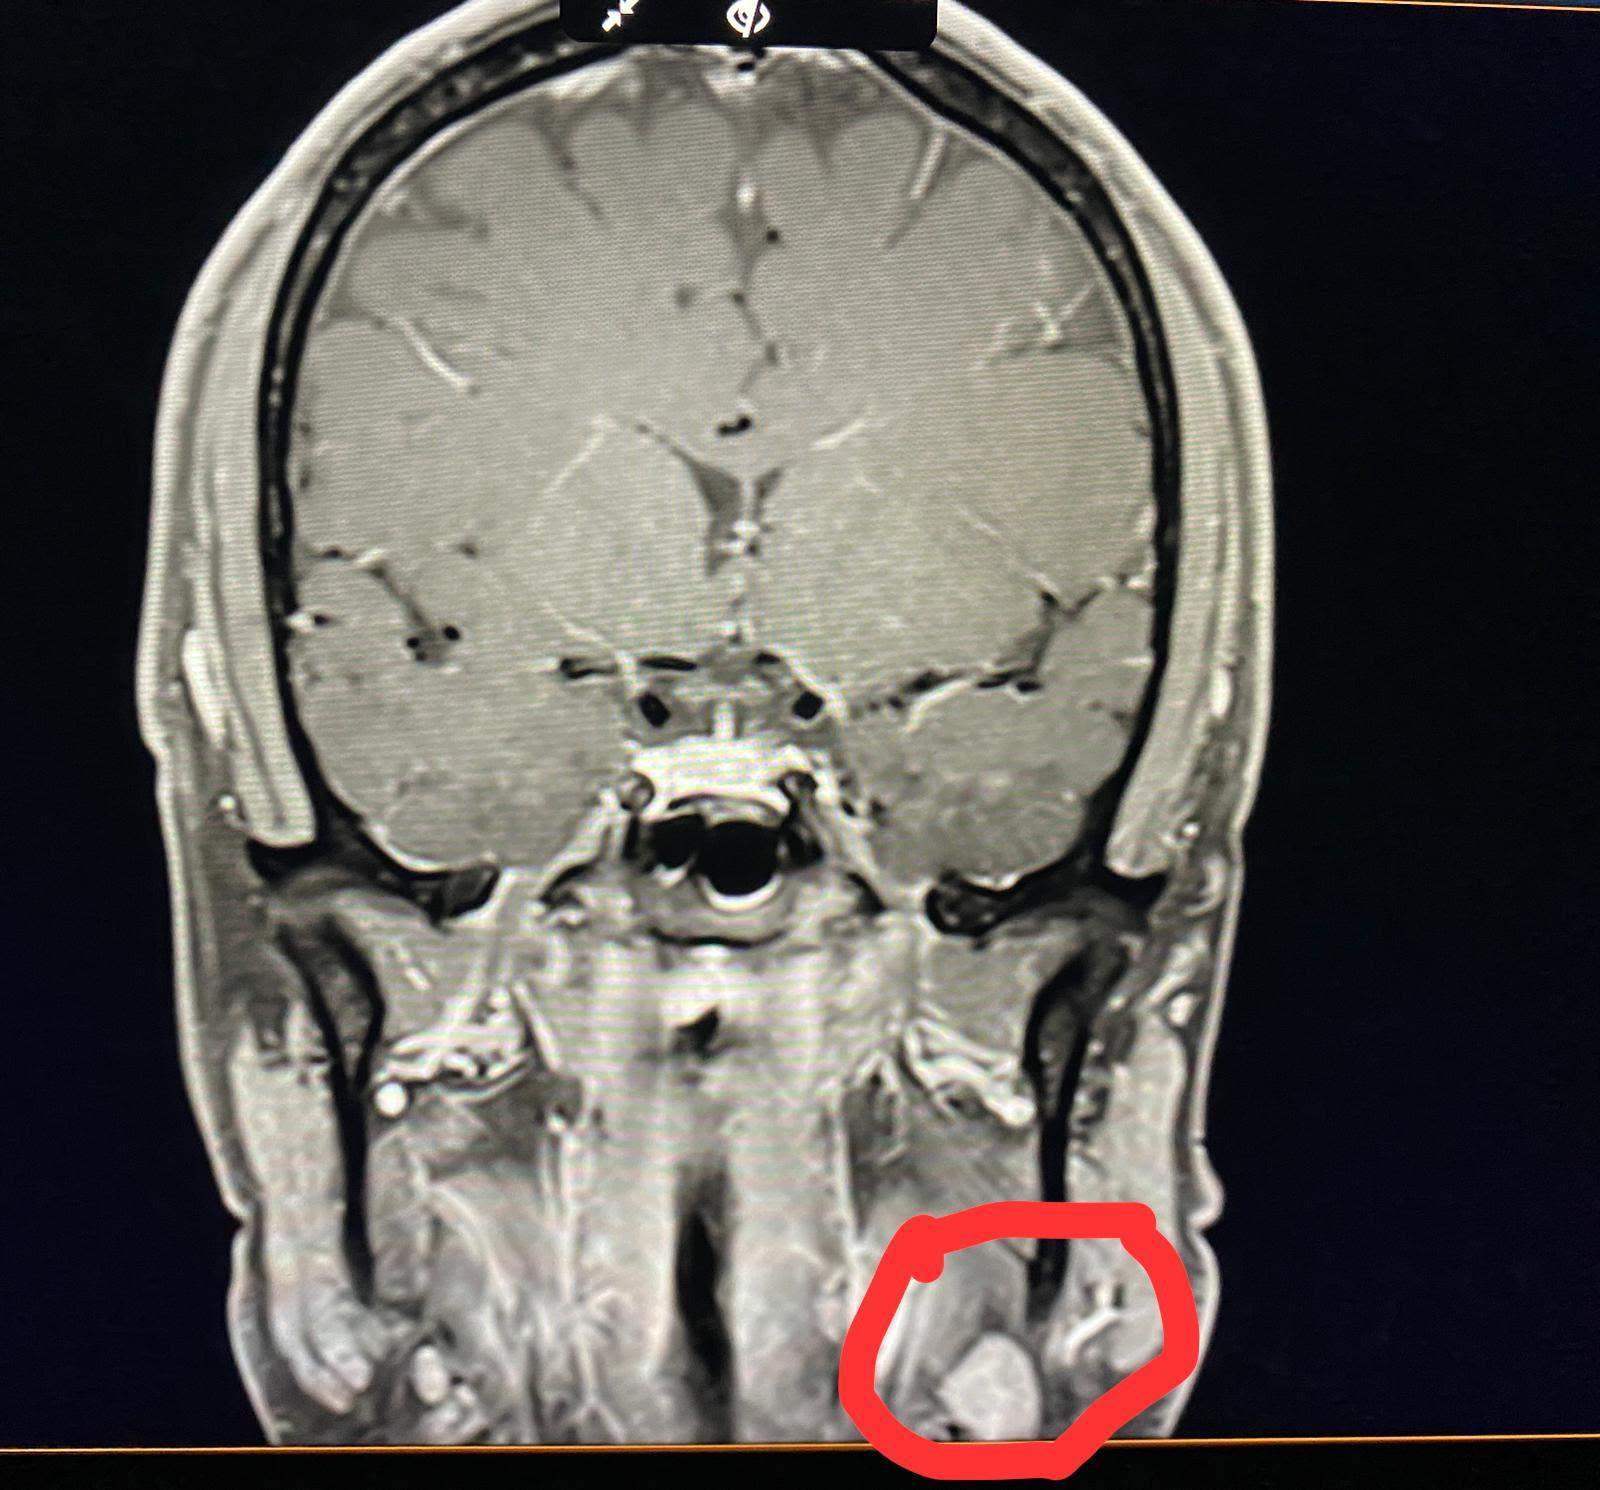

MRT Befund Schädel. Ungleich, normal? (Gesundheit und Medizin)

Was sagt dieser MRTBefund vom Kopf aus? (Gesundheit und Medizin, Gesundheit, Medizin)

MRT Schädel, was ist das? (MRT Befund, Kontrastmittel)